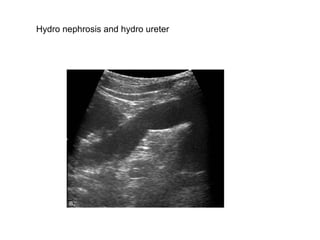

Hydronephrosis and hydroureter

Hydro nephrosis and hydro ureter